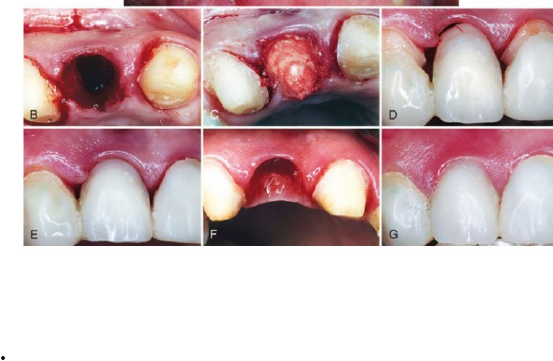

Q

Provisional prosthesis placed to develop the ovate pontic receptor site

• Maintains interdental papilla

• Develops the pontic receptor site